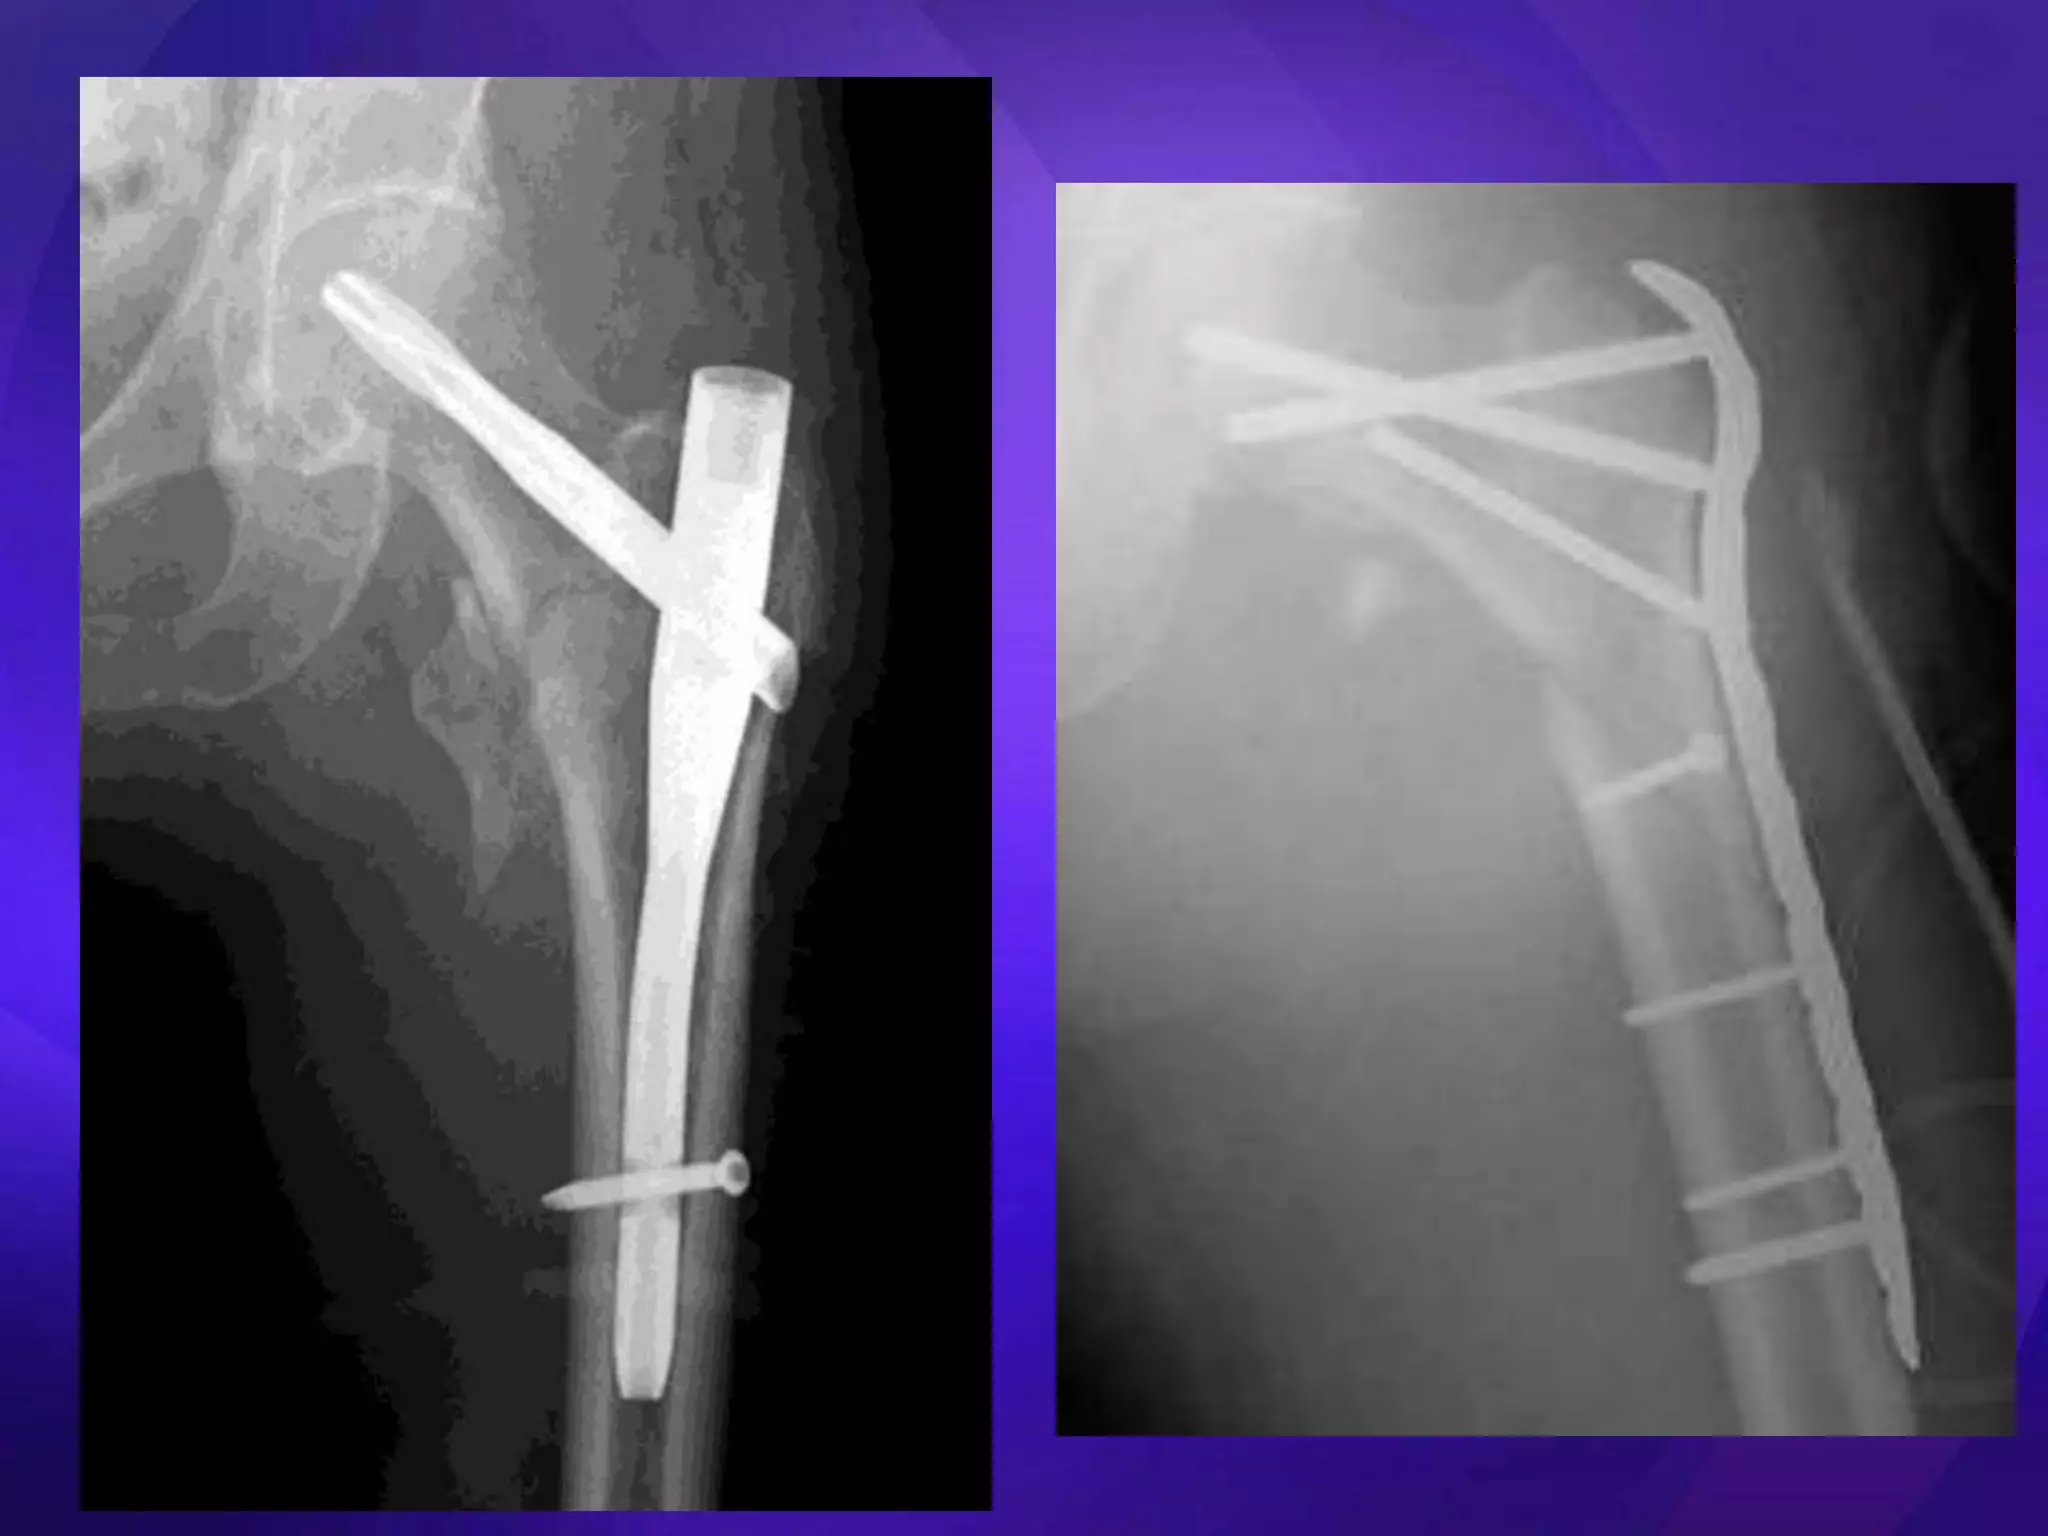

• Key issues – Medial cortical buttress – Reduction (esp varus deformity) • Extramedullary – ORIF – DHS, Medoff Sliding Plate, DCS, blade plate, locking plates • Intramedullary – Centromedullary – Cephalomedullary – Short vs long

Technically demanding • Soft tissue dissection • Plate/ screw breakage • 30% failure – Elderly – Unstable #s – Early weight bearing • Nonunions

• Easier toinsert than blade plate • Plate/ screw breakage • 20-30% failure – Elderly – Unstable #s – Early weight bearing • Nonunions

• Resist axialloading better • Less stiff in torsion • Closed Rx • Short nails = femoral shaft – Preserve fracture biology fracture • Decreased moment arm • Femoral head screw cut on implant out • ? Autogenous grafting during reaming • Segmental/ pathological # • >97% union